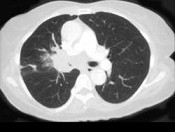

- 单项选择题男,56岁, 咳嗽,咯血1月余, 有吸烟史30余年,结合CT检查, 最可能的诊断是 ( )

E、中央型肺癌